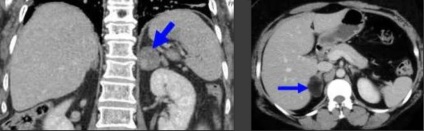

- unenhanced CT: densitate 10 HU este vysokuyuchuvstvitelnost (79%) și specificitate (96%).

10% -40% au puțină grăsime (≥10HU), astfel adenoamelor numita "lipid-săraci" și sunt considerate nesigure, este opacifierea necesar (după 1 min și 15 min).

CT.

Sindromul Cushing. Hiperplazia Makronodulyarnaya cu extinderea glandelor suprarenale (MHMAE) cu denaturarea glandelor suprarenale

CT.

Sindromul Cushing.

CT. Periph. câștig. 50-90 HU, scade treptat. Calcifiere poate fi singurul simptom rezidual.